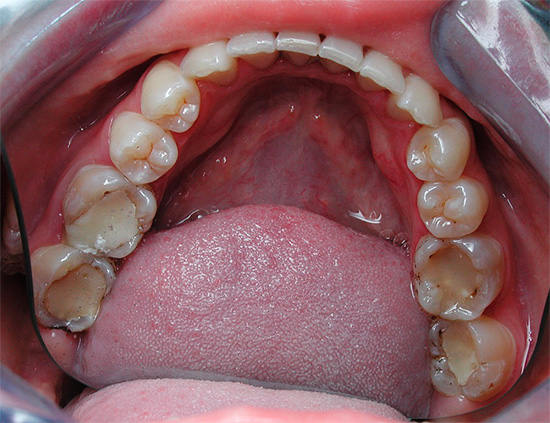

E poi nella foto: la cavità orale con i denti colpiti dalla carie delle fessure. Linee scure visibili, sebbene non grandi, ma chiaramente visibili sui molari. L'installazione di otturazioni qui non può più essere evitata, ma è del tutto possibile prevenire lo sviluppo della pulpite.